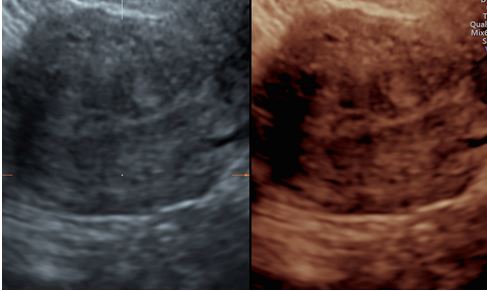

Immagini in 3d di adenocarcinoma endometriale in cui si denota un’infiltrazione del miometrio superiore al 50% dello spessore miometriale e assenza di coinvolgimento dello stroma del canale cervicale.